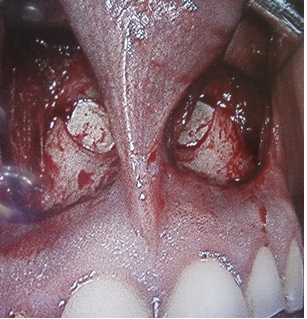

This case describes a technique of insertion of costal cartilage graft through an incision in the deep of sulcus gingiva and lip superior at the level of pyriform aperture, detachment of mucoperiosteal and building a pocket that where will be inserted the graft. After diagnosed the ENS, clinically and using the 6-item questionnaire (ENS6Q), a CT is necessary for planning the surgery, where we can observe a total inferior nasal turbinate removed Figure 1.

Figure 1 CT showing the inferior nasal concha removed.